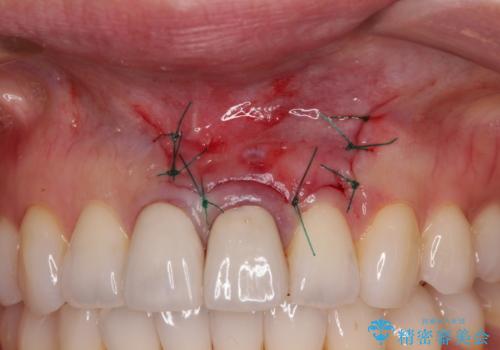

歯根端切除術では、術後に歯肉ラインが偏位し、セラミッククラウンと歯の境目が目立つことがありますが、患者様と相談の上、②歯根端切除術にて治療を行うこととしました。

半年強経過した際のレントゲン写真では、処置前のレントゲン透過像と切除した歯根部分がしっかりと歯槽骨となっている様子が認められました。